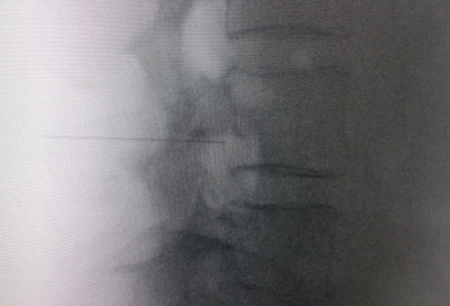

Figura 2